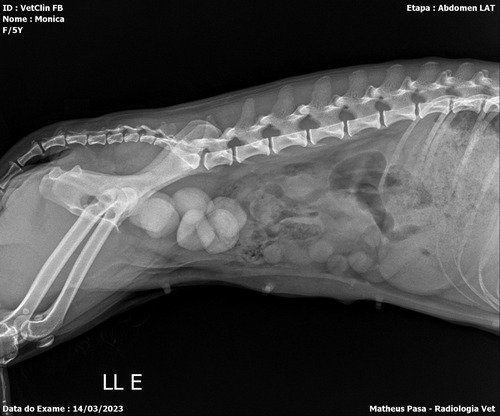

Vamos la, a um mês minha tia resgatou uma cachorrinha linda e amorosa, mas com uma história muito triste, ela veio de um lar onde era espancada todos os dias ( onde qualquer pessoa q fale alto, faça qualquer gesto brusco, ela faz xixi de medo), minha tia acabou nos oferecendo para ficarmos com ela, nossa linda momo, ela foi castrada pela Zoonoses dois dias antes de pegarmos ela.., pensem num amor de animal, como ela faz muito xixi, optamos por colocar fraldinha nela… uma alegria ela… notamos q os olhos dela está voltando a ter brilho… adotou todos da cosa como seus novos país.. mas logo na primeira semana notamos que o xixi dela estava com sangue, levamos ela onde foi castrada e nos disseram q poderia ser q ela foi castrada no período do cio… e até mesmo seria uma limpeza… mas passaram medicamentos, no inicio funcionou o xixi voltou ao normal, mas percebemos que ela tinha dores , e logo voltou o sangue no xixi junto com sangue coagulado.voltamos levar ela para ver o que tem de errado, e acabamos de descobrir que nosso novo bebê tem mais de seis cálculos renais enormes e que a bexiga pode se romper a qualquer momento, Ela está internada e sendo medicada, hoje será a cirurgia dela, mas como o custo de cirurgia, internamento ,medicação e alimentação (que será diferenciada, vai passar dos $3500,00. alguma coisa consegui… mas estás custas maiores não temos condições de arcar… então peço que ajudem esse serzinho qué foi tão violentado (provavelmente era matriz reprodutora) onde só apanhava , que nunca teve amor. as doações podem serem feitas pelo pix 46991109556